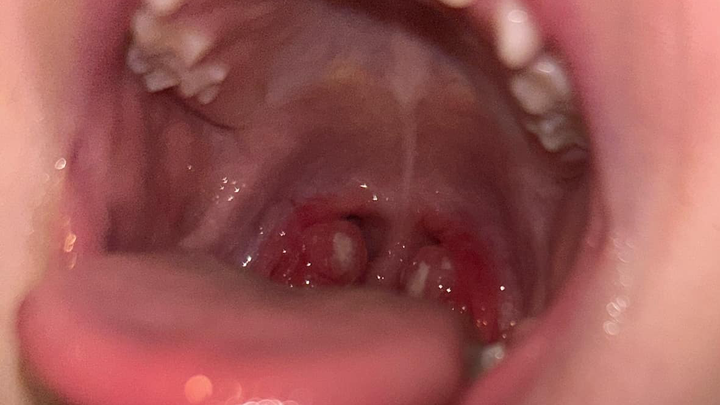

She can’t breathe through her nose at all. Eating is exhausting for her. Drinking is painful. She barely sleeps because she wakes up gasping for air. And worst of all—she can’t hear. I have to raise my voice just for her to understand me, and it breaks my heart to see her so disconnected from the world around her.

Doctors have told me she needs urgent surgery to remove her tonsils and adenoids and to have grommets placed in her ears. Without it, she will continue to live in pain, struggling to do the things every child should be able to do with ease. As there is a 18 month waiting list to have surgery in a public hospital, we have no choice but to have the surgery in a private hospital. The cost of this surgery is $6,000—an amount that, as a single mom, I simply cannot afford on my own.